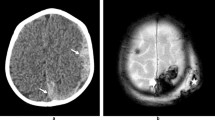

The specific case of mixed-density collections warrants discussion. Although mixed-density SDHs may reflect acute-on-chronic bleeding, they should not be taken as a priori evidence of injury of multiple ages. Hyperacute bleeding, acute hemorrhage with sedimentation levels, and inhomogeneous hematohygromas can all present as mixed-density collections [24, 25] (Fig. 2). A descriptive approach to the density or attenuation of SDH on CT is recommended, rather than a dogmatic assertion of timing.

5-week-old female presented with an acute onset of obtundation, fixed and dilated right pupil, and coagulation studies consistent with hemorrhagic disease of the newborn. Axial CT image demonstrates a right mixed-density SDH (white arrows), found to be admixed clotted and unclotted blood at subsequent surgical decompression. Note that unlike the typical SDH of AHT, there is significant associated mass effect with midline shift, right lateral ventricular effacement, and left lateral ventricular entrapment

During their evolution, SDHs often demonstrate a layering sedimentation level, and the imaging characteristics of the serous fraction will typically approximate that of simple fluid, which can be erroneously interpreted as reflecting chronicity. Dating should be estimated from the dependent sediment layer [66] (Fig. 3).

4-month-old male presented with status epilepticus, facial bruising, and diffuse multilayered RH after fall from bed. a, b Axial T2-weighted and T1-weighted images obtained 1 day after presentation demonstrate bilateral holohemispheric subdural collections which approximate CSF signal intensity (white arrows), likely subdural hygromas. There is a dependent T2 hypointense, T1 isointense sediment layer on the left (black arrows), suggesting recent hemorrhage. Watershed HII was also present, not shown

In the presence of negative intradural pressure related to parenchymal volume loss or intracranial shunting, a small subset of hygromas may persist and form enhancing vascular neomembranes along the outer then inner margins [24] (Fig. 4). Repeated spontaneous hemorrhage from these membranes transforms the collections into chronic SDHs [46, 62•]. They may be relatively simple in appearance initially, but can assume an increasingly loculated configuration with increasing mass effect over time. Enhancing neomembranes are estimated to become apparent between 10 days and 3 weeks after injury [46, 65], and are one of the few reliable indicators of non-acuity in subdural collections.

4-month-old male imaged 1 month following acute bilateral SDH related to AHT. a Coronal T2-weighted image shows bilateral subdural collections. The dura can be identified as a thin hypointense line (white arrows) between the collections and the subarachnoid space. A loculation is present on the right (black arrows) containing blood products with different signal intensity. Note the mass effect on the subjacent brain surface. b Coronal contrast-enhanced T1-weighted image shows enhancing neomembranes (white arrows) in continuity with the loculation, confirming chronic SDH with superimposed rebleeding. Such rebleeding can occur with minimal or no trauma and does not in itself suggest repeated abuse